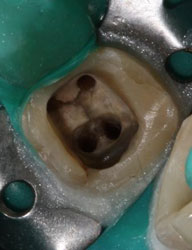

![]() | Вначале врач делает доступ к каналу (-ам) зуба. В разных зубах их, как правило, от 1 до 4…бывает и больше. На этом фото два отверстия по углам полости зуба - это и есть входы в корневые каналы |

На этом рентгеновском снимке видны, в первую очередь, «пустые» корневые каналы и довольно больших размеров очаг воспаления (то, что часто называют гранулемой, кистой) на верхушке одного из корней. В общем итоге в одном зубе был сконцентрирован целый букет ошибок и недоделок, одним словом, это образец недобросовестной работы стоматолога. Я стараюсь о коллегах всегда говорить или хорошо или молчать, но в данном случае надо смотреть правде в глаза – зуб загублен именно стоматологом. Никаких объективных сложностей для качественной работы изначально здесь не было. Зато появились теперь. Прогноз на будущее для таких зубов всегда строится, исходя из 2 основных проблем – насколько приведет к успеху повторное лечение каналов и насколько будет успешной попытка адекватного восстановления зуба после этого. Оценив вероятность долговременного успеха этих двух составляющих, можно решать, стоит ли «спасать» зуб от щипцов хирурга. Ведь, в любом случае, лечение стоит денег, а гарантировать результат здесь невозможно. Можно только предполагать вероятность успеха. В данном случае каналы не выглядели непроходимыми. Да и восстановить зуб коронкой, даже несмотря на большую степень разрушения, все еще представлялось возможным. А потому было принято решение о начале лечения.